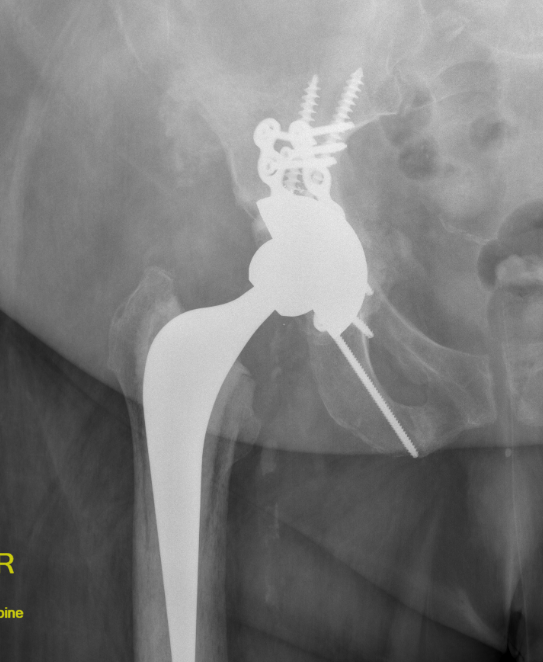

Intra-operative acetabular fracture

Postoperative acetabular fracture treated with double posterior plating